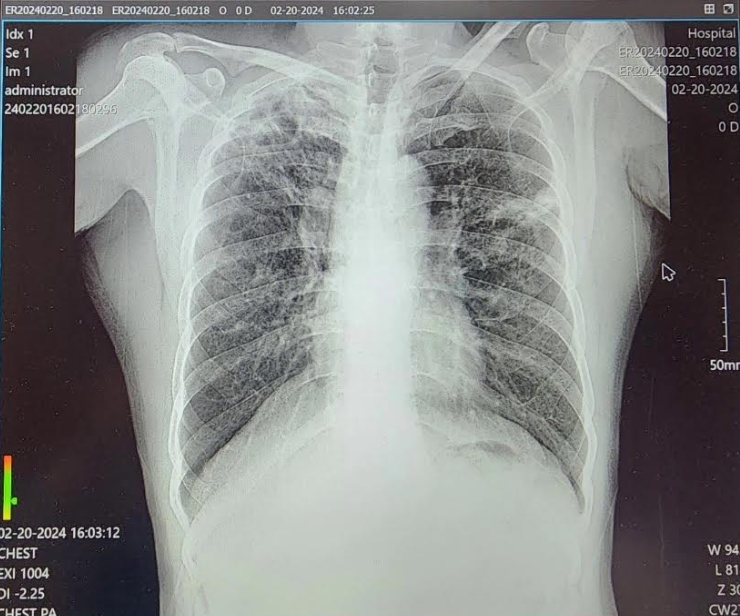

일반외과 원장은 휴대용 저선량 X-ray 장비(MINE ALNU, NOOKA)를 지인에게 빌려와서 사용했는데 휴대용임에도 불구하고 생각보다 해상도가 높고 깔끔한 영상을 얻을 수 있어 매우 만족스러웠다.

휴대용 X-ray는 카메라 형태의 X선 발생장치와 영상 수신장치인 휴대용 디텍터, 그리고 그 정보를 받아 영상으로 출력하는 노트북으로 구성돼 있었다. 디텍터는 가로×세로 46cm로 부피가 다소 컸지만, 백팩처럼 메고 이동하기에는 충분했다. X선 발생장치도 일반 디지털카메라보다 약간 큰 정도로 휴대에 어려움이 없었다. 다만 스탠드가 없이 환자가 디텍터를 직접 들거나 보조자가 옆에서 들어주어야 했기 때문에 표준 촬영 자세를 취하지 못함으로 인한 오류가 발생할 수 있었다.

현지에서는 인터넷 사정과 전기공급이 매우 열악한 지역에서 진료했고, 와이파이 오류 등으로 촬영에 제한이 생기기도 했다. 그러나 단순 흉부 X선 촬영에서 양쪽 폐야가 분명하게 나타났고 늑골횡격막각(CP angle)과 폐문부(Hilum)의 혈관음영도 자세하게 확인할 수 있었다.

한 환자에게서는 폐문부의 이상음영으로 폐암(의증)을 진단했으며, 다른 환자에게서는 폐엽의 섬유상 패턴으로 결핵을 진단했다. 무릎과 경추도 일반적인 X-ray와 비교해 전혀 나쁘지 않은 촬영 결과가 나타났다.

다만 비만인이거나 요추의 경우 피폭선량이 다소 부족해 뿌옇게 보이는 저노출 영상으로 보여지기도 했다. 자세한 판독이 필요한 경우 국내의 영상의학과 전문의에게 사진을 전송해 원격 판독을 의뢰했다.